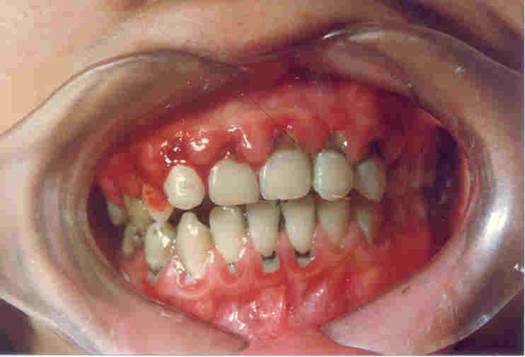

Chải răng ngay sau khi ăn, tối trước khi ngủ với kem có fluor là biện pháp can thiệp khoa học, dễ thực hiện, rẻ tiền và hiệu quả để phòng bệnh sâu răng, bệnh nha chu. Nếu chúng ta chăm sóc răng - lợi kỹ lưỡng, chúng ta có thể giữ răng chắc khỏe suốt đời.

Chải răng giúp răng và lợi sạch, tự tin khi giao tiếp, phòng bệnh sâu răng và nha chu.